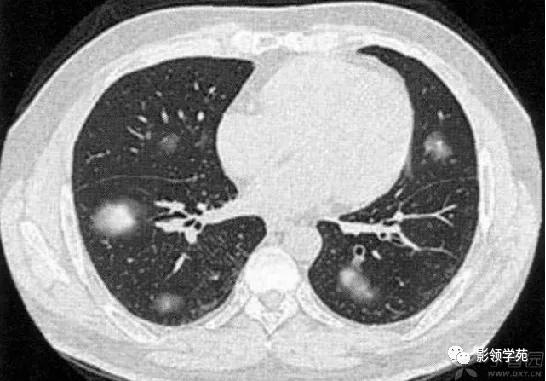

病例3:双肺多发结节伴空洞,部分空洞见气液平面。

胸部CT检查有阳性发现者占97%,包括多发性肺结节、肿块、楔形病灶、片状浸润阴影、空洞、气道狭窄或溃疡、肺出血等。肺部Wegener肉芽肿CT征象多样,典型的影像学特点是“三多”,即多发性、多样性、多变性。多发性指肺内多处病变,散在双侧肺野,尤以双下肺好发。多样性指病变形态及新旧不一,病变形态多样,呈结节、实变、空洞及条索影等,结节及空洞较为常见。空洞形成是Wegener的重要影像特点,环形空洞是此病的特征。浸润、空洞及结节等多种形式常同时存在。多变性指病变部位、大小及形态处于动态变化之中。

肺内多发结节和肿块是肺Wegener肉芽肿最常见的影像征象,表现为两肺散在分布、多发大小不等类圆形结节或肿块影,以两肺中下野分布多见。部分结节和肿块内可见空洞,洞壁多较厚,内缘光滑或不规则,空洞呈边缘性强化。合并感染时空洞内可形成液-气平面。结节或肿块周围一般都有较短毛刺,部分病灶有长毛刺与邻近的胸膜相连,表现为胸膜凹陷征。这与病理上结节周围存在大量成纤维细胞以及以纤维化形式愈合有关。